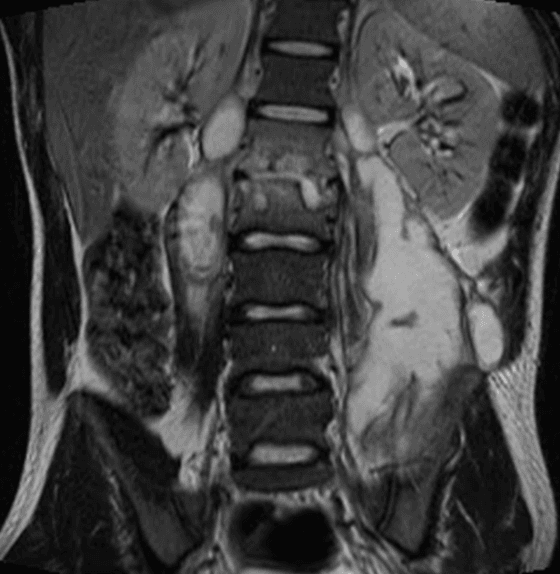

Figura 1.